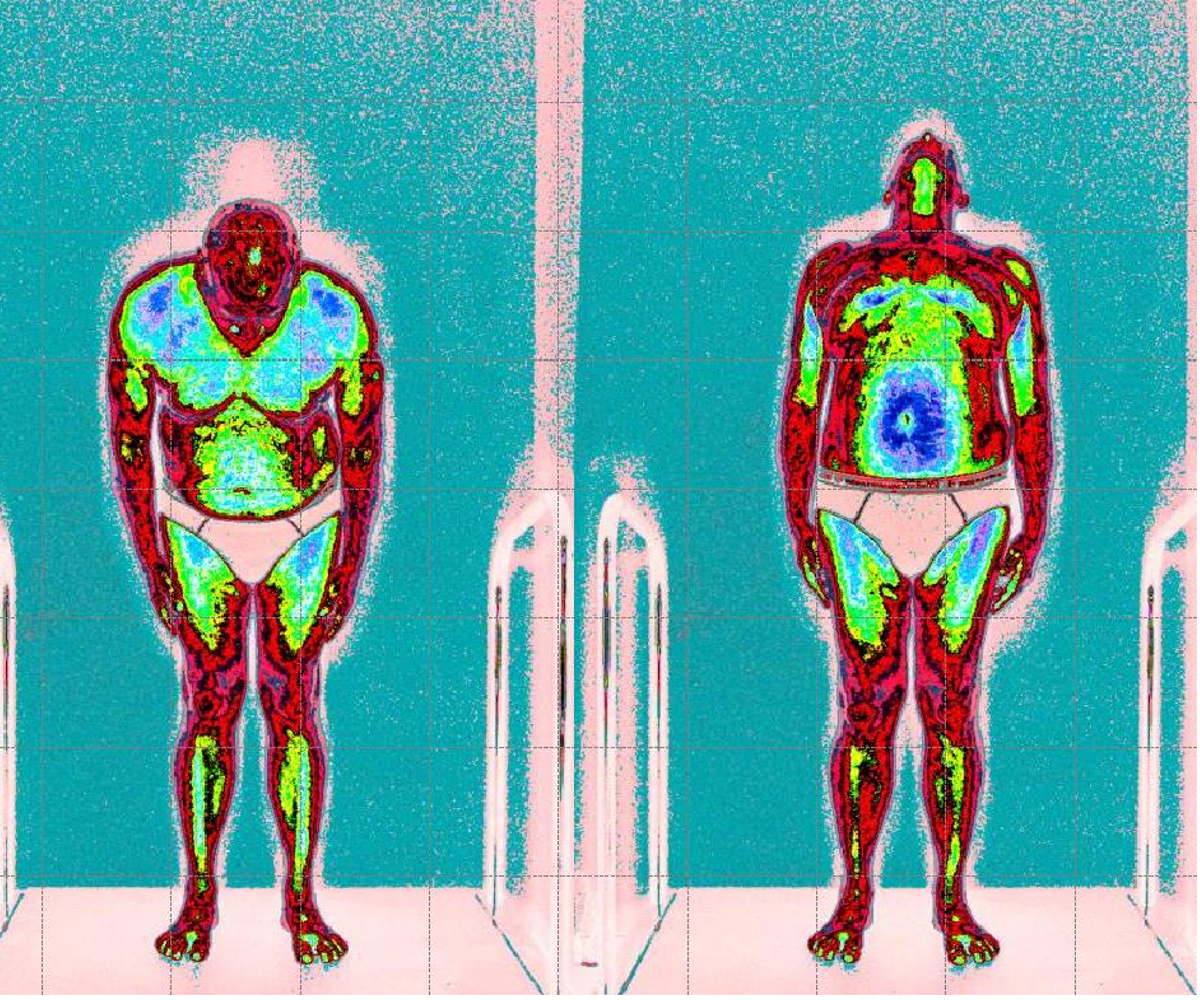

In questa immagine possiamo vedere il cliente paziente con lombalgia acuta causa discopatie multiple

Prime foto maggior tensione globale della muscolatura anteriore (colore blu scuro)

Dopo il trattamento con Renovatio, riduzione netta della tensione muscolare globale (colore azzurro, normalità di tensione)

Sintomatologia riduzione del dolore e maggior flessibilità del tronco.

Leggenda: colore rosso inattivazione tensione muscolare

Verde, minima tensione muscolare

Azzurro normale tensione muscolare

Blu scuro, aumento della tensione muscolare